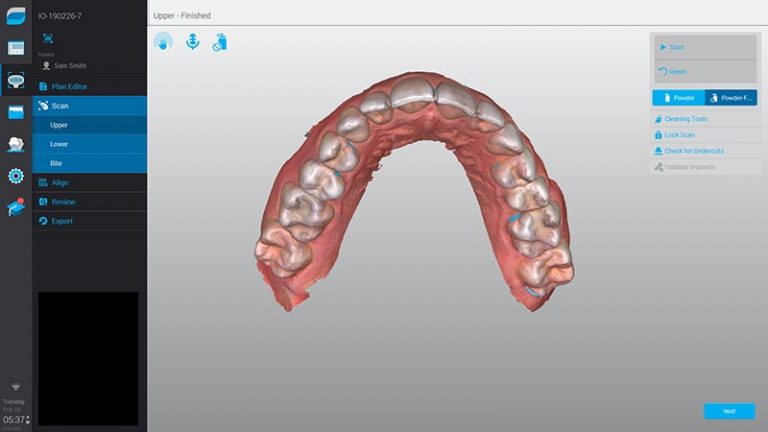

Nosso Scanner elimina algumas etapas clínicas e ainda evita possíveis erros de distorções, garantindo mais precisão para o seu processo.

Com nossa tecnologia a confecção de aparelhos, lentes de contato e até mesmo próteses é extremamente simples, eliminando completamente a necessidade da moldagem.

Em apenas alguns minutos todas as informações necessárias são coletadas, sem nenhum processo desconfortável.

Resultados em tempo real são prontamente enviados e analisados pelos profissionais responsáveis, reduzindo drasticamente o tempo necessário para as próximas etapas.